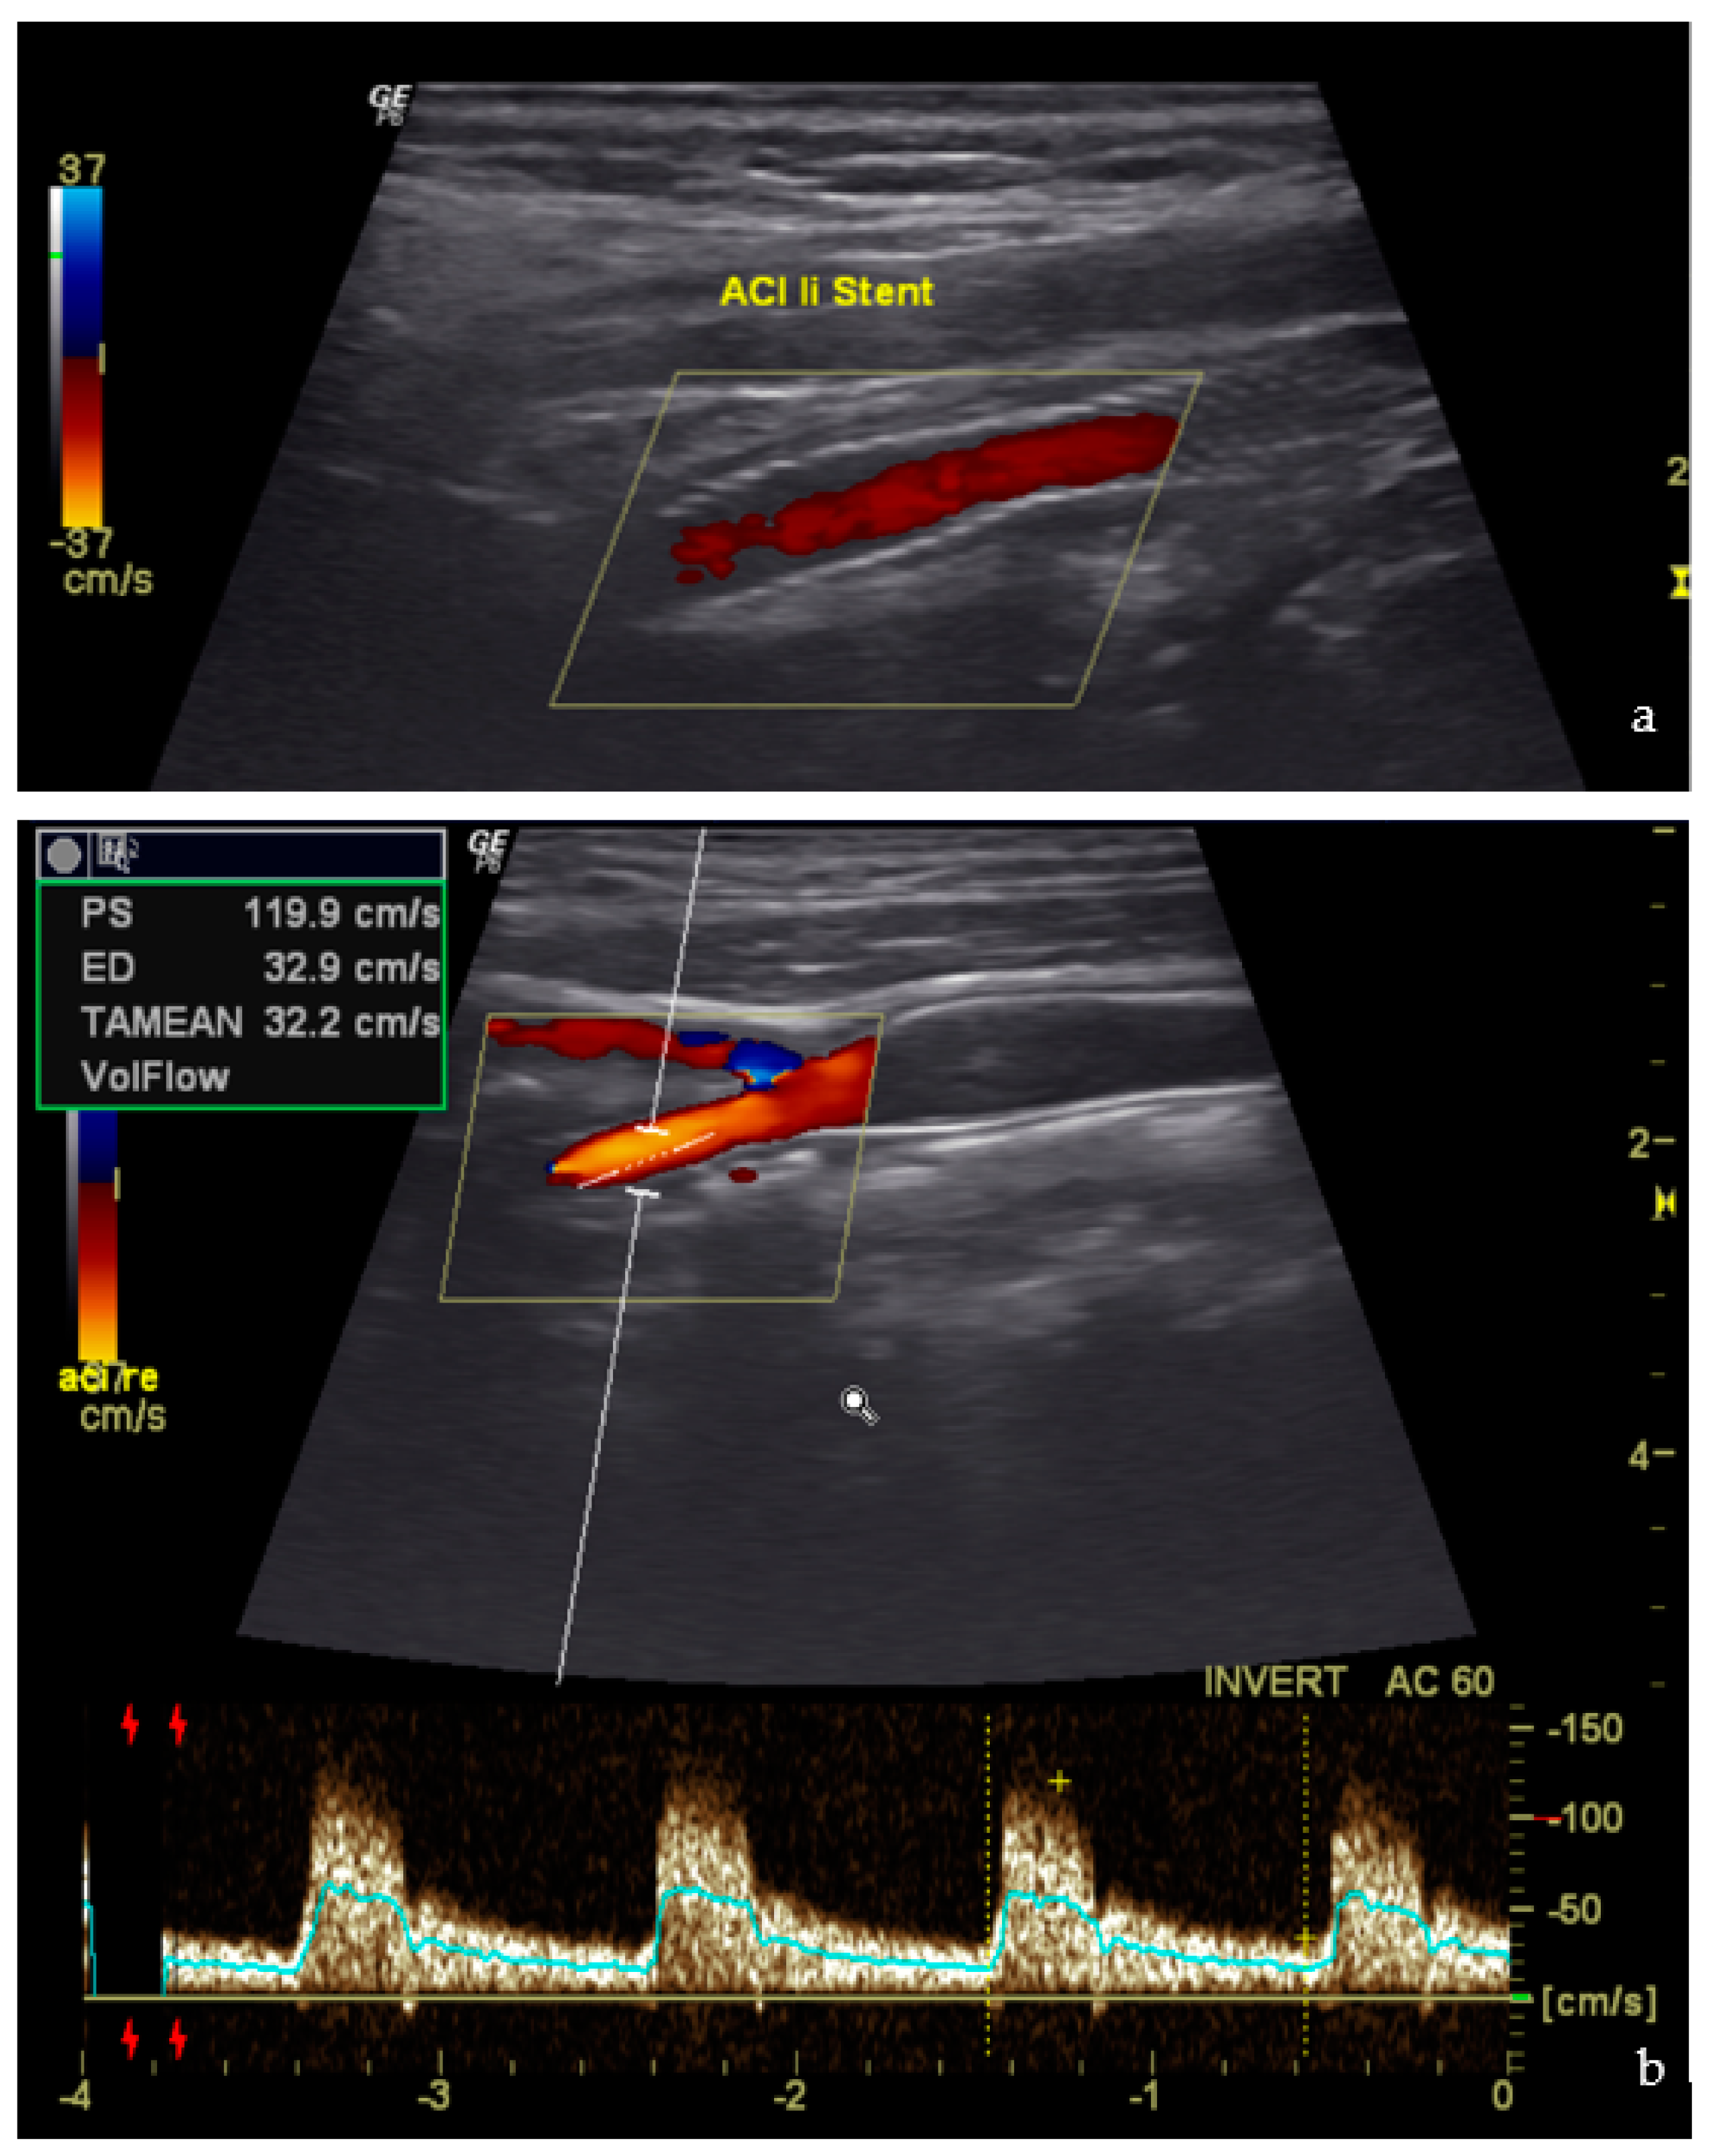

Postoperative duplex ultrasound was performed on all patients before discharge. No signs of restenosis, carotid dissection, or thrombotic stent occlusion were evidenced. Figure 7 shows an example of normal findings on the postoperative duplex ultrasound.

Figure 7.

Postoperative ultrasound (a) Duplex of the Stent course (b) Doppler of the ICA.